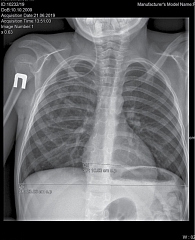

Рис. 3. Рентгенологическое исследование органов грудной клетки. Сердечно-грудной индекс – 0,44 (горизонтальный размер тени сердца в норме – 10,52 см)

При проведении рентгенологического исследования сердечно-грудной индекс был в пределах нормы – 0,44 (горизонтальный размер тени сердца – в норме (10,52 см)) (рис. 3).